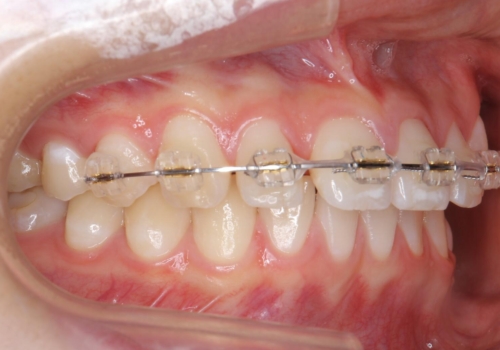

- ワイヤー矯正

- 9ヶ月

- 前歯のすき間を気にして来院。

全体矯正ではなく部分矯正で治療することになりました。

その代わり、すき間をすべて閉じるのは難しく、両脇の目立たないところに集めて治療終了しています。